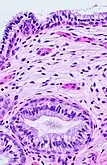

Transformation zone mucosa, when the squamocolumnar junction has a gradual transition. It consists of a mix of stratified squamous epithelium and mucinous glands. H&E stain.

Histology of endocervix, with mucinous columnar epithelium and mucinous glands. H&E stain.

The endocervical mucosa is about 3 mm (0.12 in) thick and lined with a single layer of columnar mucous cells. It contains numerous tubular mucous glands, which empty viscous alkaline mucus into the lumen.[4] In contrast, the ectocervix is covered with nonkeratinized stratified squamous epithelium,[4] which resembles the squamous epithelium lining the vagina.[17]:41 The junction between these two types of epithelia is called the squamocolumnar junction.[17]:408–11 Underlying both types of epithelium is a tough layer of collagen.[18] The mucosa of the endocervix is not shed during menstruation. The cervix has more fibrous tissue, including collagen and elastin, than the rest of the uterus.[4]

In prepubertal girls, the functional squamocolumnar junction is present just within the cervical canal.[17]:411 Upon entering puberty, due to hormonal influence, and during pregnancy, the columnar epithelium extends outward over the ectocervix as the cervix everts.[15]:106 Hence, this also causes the squamocolumnar junction to move outwards onto the vaginal portion of the cervix, where it is exposed to the acidic vaginal environment.[15]:106[17]:411 The exposed columnar epithelium can undergo physiological metaplasia and change to tougher metaplastic squamous epithelium in days or weeks,[17]:25 which is very similar to the original squamous epithelium when mature.[17]:411 The new squamocolumnar junction is therefore internal to the original squamocolumnar junction, and the zone of unstable epithelium between the two junctions is called the transformation zone of the cervix.[17]:411 Histologically, the transformation zone is generally defined as surface squamous epithelium with surface columnar epithelium or stromal glands/crypts, or both.[20]